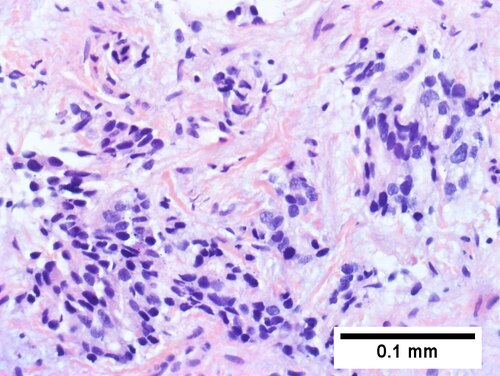

Cholangiocarcinoma, intrahepatic, with associated abscess. A. Aberrant spaces (arrows) contrast with the scar to the regions left and, at right, hemosiderin laden macrophages amid granulation tissue [40X]. B1. Disorderly spreading glands (black arrows) associated with atypical single cells (cyan arrows) have nuclei that contrast with those of the normal bile duct (blue arrow) with its associated artery (green arrow) [200X]. C. PAS without diastase shows disorderly spreading, aberrantly shaped glands at left (arrows) and red degenerated hepatocytes to right [200X]. D. PAS with diastase shows proliferating bile ducts to left, one with highly aberrant nuclei (black arrow), highly atypical cells at middle (green arrows) with sometimes incomplete (cyan arrows) acini, and normal liver at right (blue arrow) [200X]. E. CK7 immunostain shows proliferating glands at left and a disorderly spread of single cells and cell groups at right, amid hepatocytes [200X]. F. CK7 immunostain at higher power shows the stained cells have aberrant nuclei [400X].